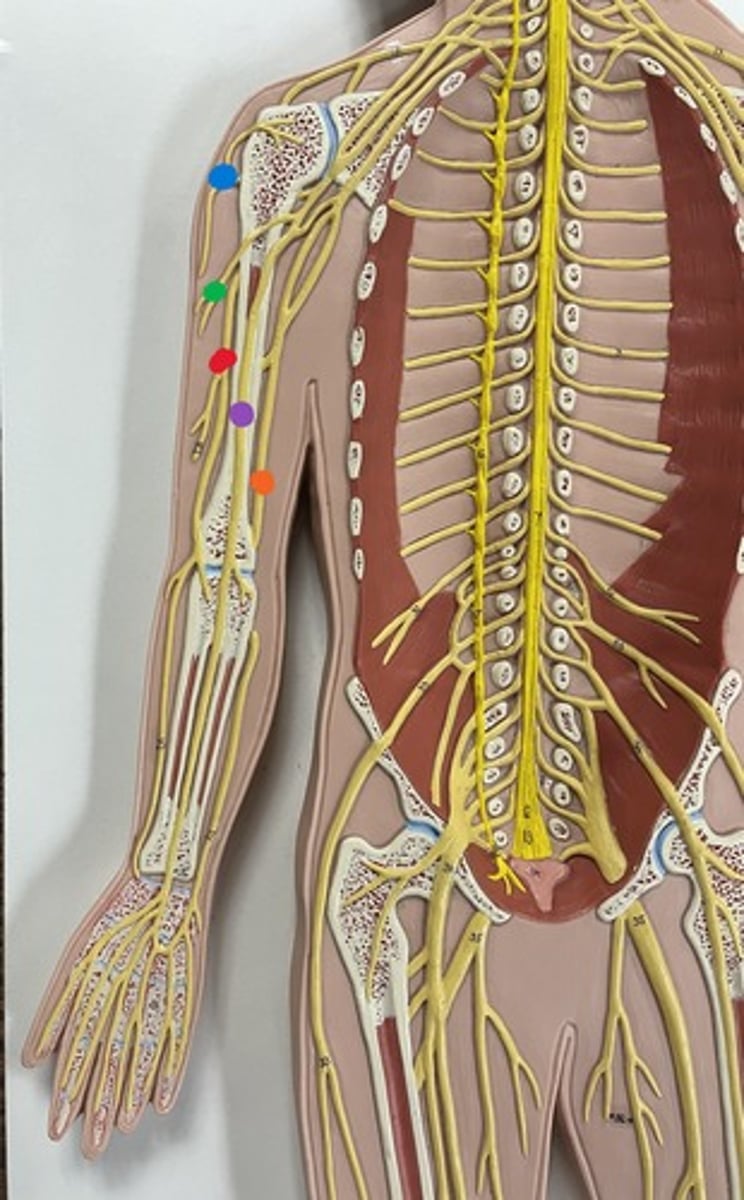

Brachial plexus

Axillary nerve

blue

Musculocutaneous nerve

green

Median nerve

purple

Ulnar nerve

orange

Radial nerve

red